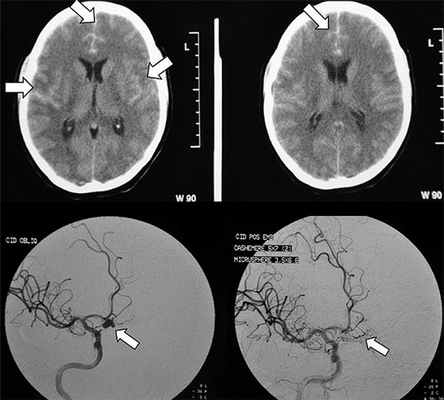

Рисунок 2. Как выглядит субарахноидальное кровоизлияние на диагностическом снимке. Источник:Brazilian Journal of Psychiatry (Creative Commons Attribution Non-Commercial License)

Больная Х., 66 лет, поступила в Институт нейрохирургии на 3-и сутки после интракраниального кровоизлияния из аневризмы. Оценка по шкале Ханта—Хесса — V степень. На момент поступления: уровень сознания — кома II, температура тела 38,0 °С. Дыхание аппаратное, искусственная вентиляция легких в режиме IPPV. Гемодинамика нестабильная с тенденцией к артериальной гипотензии. Артериальное давление поддерживалось внутривенным введением вазопрессоров на уровне 120—140/79—85 мм рт.ст. Компьютерная томография головного мозга обнаружила внутримозговую гематому в височной доле справа с субарахноидальным распространением крови и отеком мозга (рис. 1).

Рисунок 1. Компьютерная томограмма при поступлении: определяется внутримозговая гематома правой височной доли. По данным церебральной ангиографии в области бифуркации ВСА была обнаружена артериальная мешотчатая аневризма размером 4,2×3,7 мм. Учитывая тяжесть состояния, больной был установлен вентрикулярный дренаж с датчиком внутричерепного давления (ВЧД), которое на тот момент составляло 30—32 мм рт.ст.